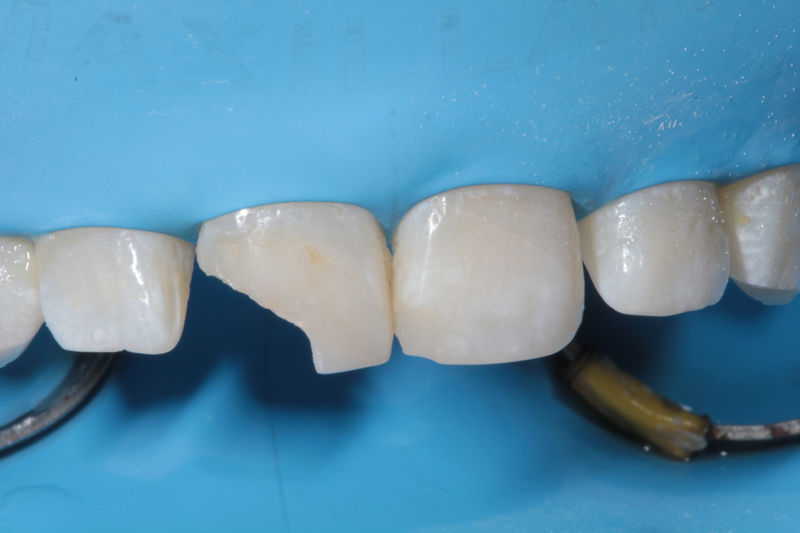

Restauraciones fabricadas en el laboratorio con materiales estéticos, los cuales cubren de manera parcial dientes posteriores. Se utilizan primariamente para restaurar dientes con caries, fracturas y/o defectos amplios. Para poder enviar el caso al laboratorio se toman impresiones utilizando materiales de impresión o técnicas modernas digitales.

Restauraciones fabricadas en el laboratorio con materiales estéticos, los cuales cubren de manera total dientes anteriores y posteriores. Se utilizan primariamente para restaurar dientes con caries, fracturas y/o defectos amplios, así como soportes de puentes. Para poder enviar el caso al laboratorio se toman impresiones utilizando materiales de impresión o técnicas modernas digitales.

Restauraciones fabricadas en el laboratorio con materiales estéticos, los cuales se usan para reemplazar dientes ausentes usando coronas como soporte. Para poder enviar el caso al laboratorio se toman impresiones utilizando materiales de impresión o técnicas modernas digitales.